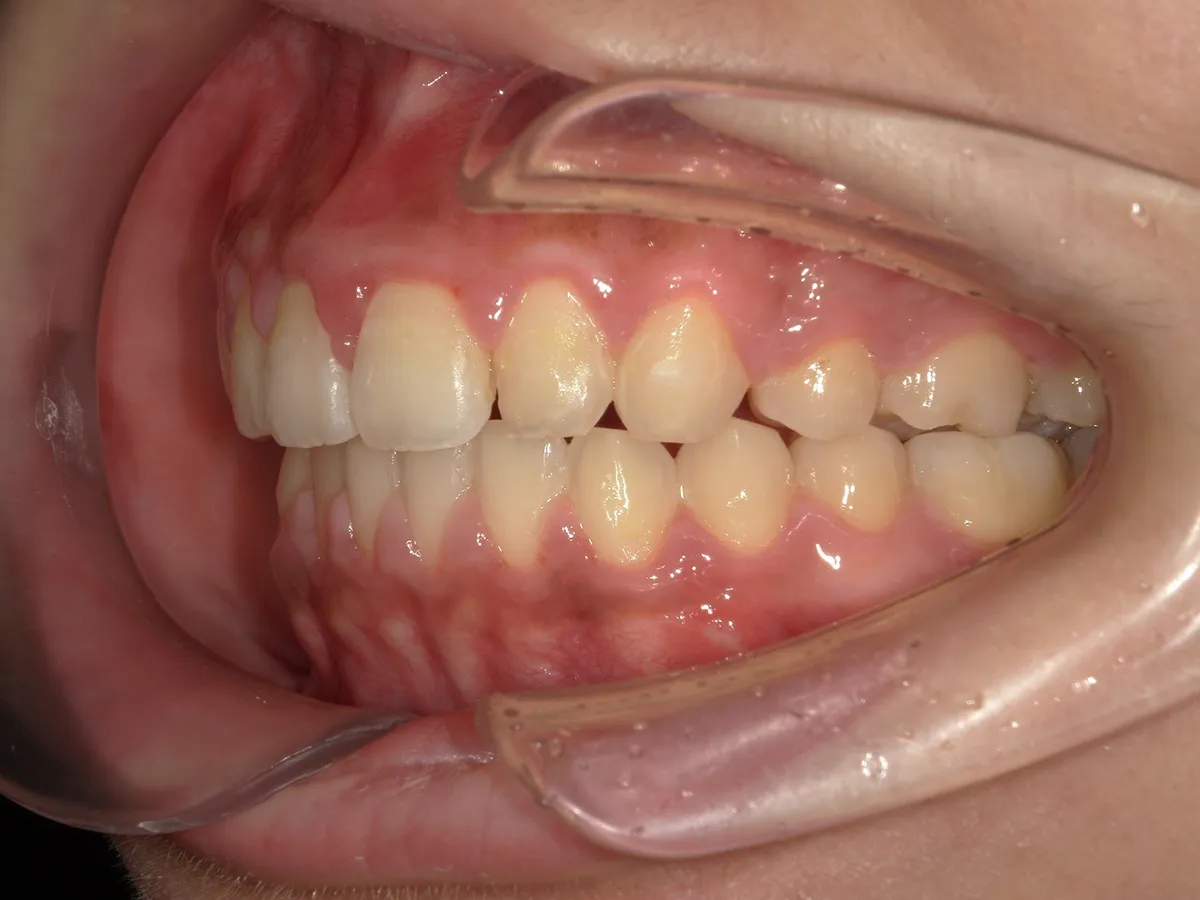

矯正歯科の症例

21歳 女性

出っ歯を治したい。

治療経過中の写真

治療方法:表側レジンブラケット+シルバーワイヤー(右上5番、E、左上4抜歯) 回数:1回/月

動的期間:2年